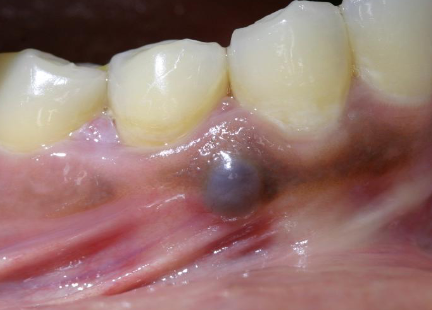

mucocele

most common on lower lip due to trauma of minor salivary gland